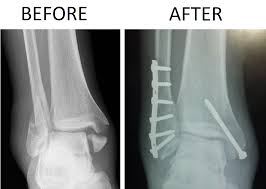

Rule out trimalleolar fracture.

what is a trimalleolar fracture

• Lateral malleolus

• Medial malleolus

• Distal posterior aspect of the tibia, called the posterior malleolus.